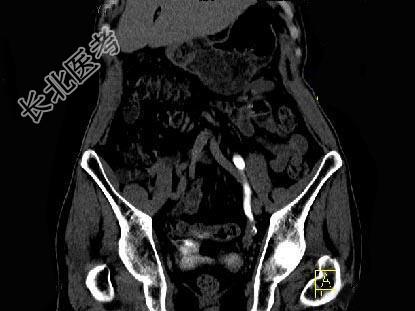

- 单项选择题男,76岁, 无痛性肉眼血尿3个月,CT检查如图所示, 下列说法错误的是 ( )

A、左侧肾盂扩张积水

B、左侧输尿管中上段扩张

C、左侧输尿管下段可见节段状不规则的软组织肿块影

D、考虑为左侧输尿管炎

E、考虑为左侧输尿管下段癌